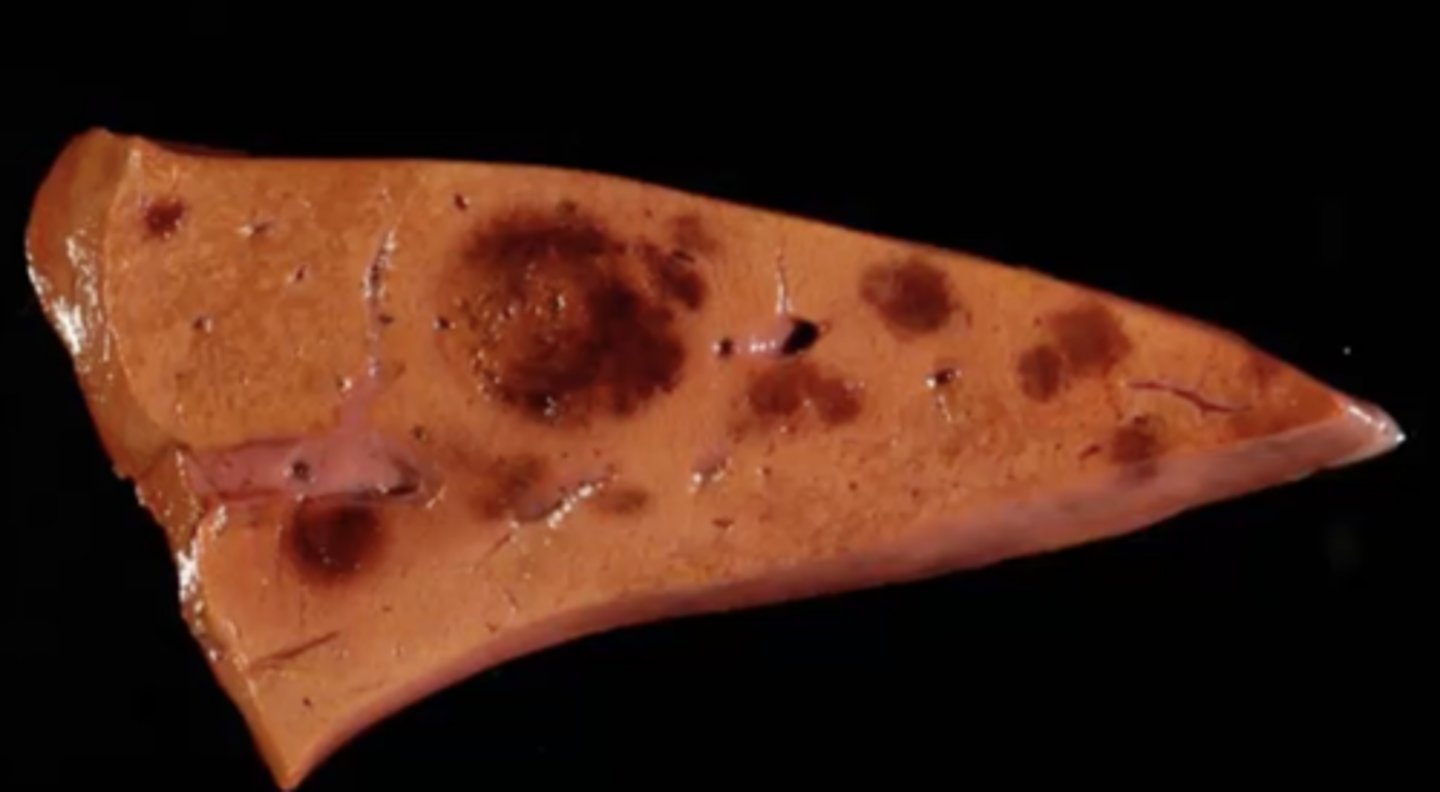

Hepatosis Dietetica

-caused by vitamin E/Selenium deficiency in rapidly growing pigs

-massive hepatic necrosis due to oxidative injury

What has caused this gross appearance of this pig liver?